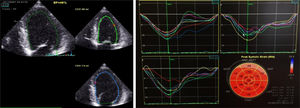

Durante o internamento na Enfermaria de Cardiologia, um cateterismo cardíaco diagnóstico foi realizado, com coronárias sem lesões (Figura 2). Não havia história familiar de IC, miocardiopatia ou morte súbita. O doente negava história recente de infeção viral ou bacteriana e nunca havia viajado para fora do país. O estudo laboratorial foi negativo, nomeadamente para vírus da imunodeficiência humana e hepatotrópicos. A função tiroideia não demonstrava alterações (avaliações prévias ao longo do seguimento na consulta de diabetes também normais), não tendo sido avaliados anticorpos antitiroideus neste contexto. Ressalvam‐se ainda outros parâmetros laboratoriais ao longo do internamento: hemoglobina (Hb) à admissão de 15g/dl, com nadir de 13g/dl, sem perdas hemáticas objetivadas; sem ferropénia funcional ou absoluta (Ferritina 326ng/mL) e sem défice de ácido fólico ou vitamina B12 (5,9ng/mL e 590pg/mL, respetivamente); vitamina B1 avaliada por protocolo nos doentes com IC / disfunção ventricular esquerda de 28ng/mL (N 16‐48). Sete dias após admissão hospitalar, um novo ETT foi realizado: ventrículo esquerdo não dilatado, com compromisso ligeiro da função sistólica (FEj estimada em 46%), com strain global longitudinal ligeiramente reduzido (‐16%) (Figura 3). Foi proposta a realização de ressonância magnética cardíaca, que o doente recusou. À data de alta hospitalar, o doente encontrava‐se em NYHA I, com proBNP de 448pg/ml, e medicado com Ramipril 2,5mg/dia e Bisoprolol 5mg/dia, além de insulina lenta para administração bidiária, tendo sido proposto seguimento em consulta de cardiologia e consulta hospitalar de diabetes.

Uma semana após a alta programou‐se a realização de um terceiro ETT, demonstrando uma função sistólica global do VE conservada (FEj 52%) com strain global longitudinal normal (‐20,2%) (Figure 4). A oito meses de follow‐up sem novos internamentos, sem queixas do foro cardiovascular.